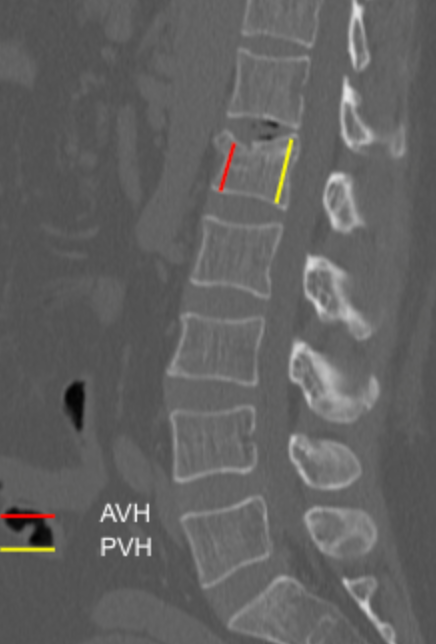

Vertebral Body Dimensions

Sagittal Index (Anterior/Posterior Height Ratio)

CT Scan